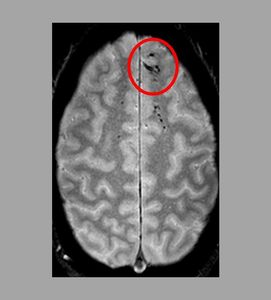

Sie sind hier: Startseite Nachrichten Gesundheit Hirn-Mikroblutungen sagen Therapieerfolg voraus Läsionen: Mikroblutungen nun sichtbar gemacht.

Läsionen: Mikroblutungen nun sichtbar gemacht.

Bild: Latour Lab/ninds.nih.gov